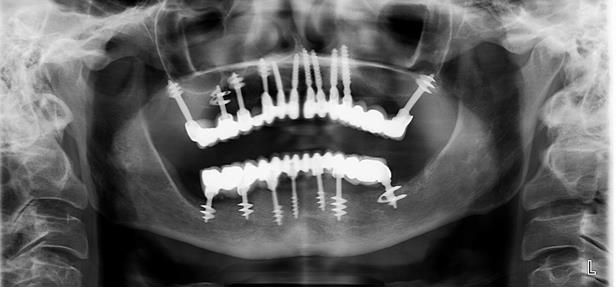

Figure 1

Panoramic radiography of patient Y before starting treatment.

Figure 2

On cone beam computed tomography, the presence of a defect in the alveolar process of the upper jaw on the left at the level of missing 24-26 teeth with transition to the anterior maxillary sinus and the cheek-alveolar ridge is determined. The sinus is made of homogeneous contents. (Fig. 1,2,3).